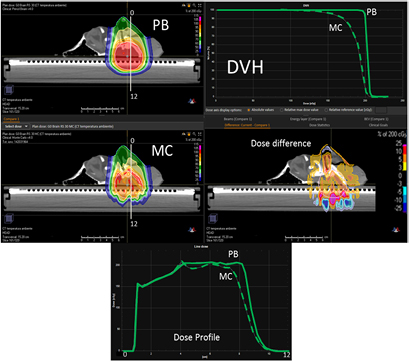

Standard image High-resolution imageIn the case of the more superficial target on the 'nose target' of the lamb's head, the dose differences between the PB and MC algorithm increase (figures 10 and 11 and table 4). For the gantry angle of 60°, the γ passing rate is also well below 95% in the case of small air gap (snout position at 24 cm, i.e. air gap of 1.5 cm) and the application of the splitting technique. For such a tangential entrance, the MC algorithm provides superior performances, matching significantly better with the measured data.

Figure 10. PB optimized dose distribution on the nose target of the lamb's head (top left) and MC recalculation (middle left) with a proton field angle of 60° and the RS 30 cm from the isocenter (i.e. air gap ~7.5 cm). The white lines represent the dose profiles' (bottom) extraction plans. On the right side of the figure, the DVHs of both the dose distributions (top right) and dose difference (middle right) are displayed.

Standard image High-resolution imageFigure 11. Dose distribution and γ analysis comparison between the MatriXX measurement and the PB or MC dose engine in a transversal plane for the lamb's head's nose target, with a gantry angle of 60° and the snout position at 30 cm. The white lines represent the dose profiles' extraction plans, the red lines are the measured data profile while the green lines represent the calculated dose distribution. The red region in the γ graph represents the area with γ > 1.